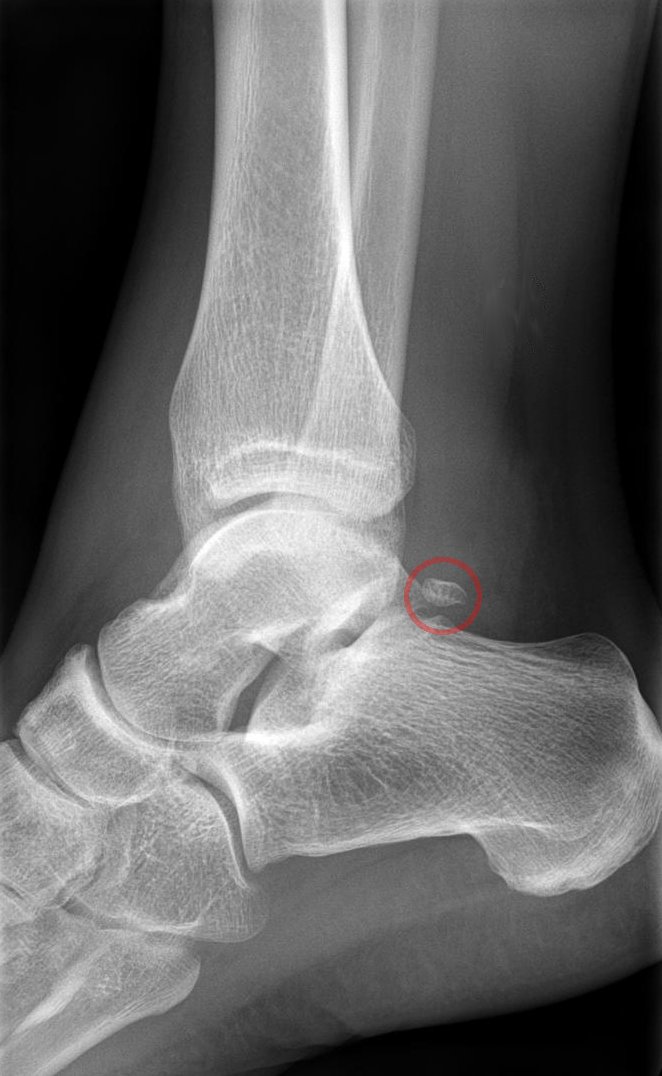

목말뼈는 혈액 공급이 원활하지 않아 골절 시 회복이 더딜 수 있다. 목말뼈 부상은 인지하기 어려울 수 있으며,[8][9] 특히 외측 돌기 골절은 방사선 사진상으로 나타나지 않을 수 있다.

4. 1. 골절

목말뼈는 혈액 공급이 원활하지 않아 골절 시 회복이 더딜 수 있다. 이 때문에 골절된 목말뼈는 다른 뼈보다 회복하는 데 더 오래 걸릴 수 있다. 목말뼈가 골절된 사람은 목발 없이 몇 달 동안 걷지 못할 수 있으며, 그 후에는 보행 보조기나 부츠와 같은 보조기를 착용해야 한다.[8][9]목말뼈 부상은 인지하기 어려울 수 있으며, 특히 외측 돌기 골절은 방사선 사진상으로 나타나지 않을 수 있다. 적절하게 인식하고 관리하지 않으면 목말뼈 골절은 합병증과 장기적인 문제를 야기할 수 있다. 2015년 연구에서는 고립된 목말뼈 몸통 골절이 이전에 생각했던 것보다 더 흔할 수 있다는 결론을 내렸다.[10]

골절된 목말뼈 몸통은 종종 탈구를 동반하며, 이는 CT 촬영을 통해 가장 잘 확인할 수 있다. 목말뼈 골절에 탈구가 동반된 경우 발목과 뒷발의 기능을 최적화하기 위해 관절 및 축 정렬을 복원해야 한다.[8]